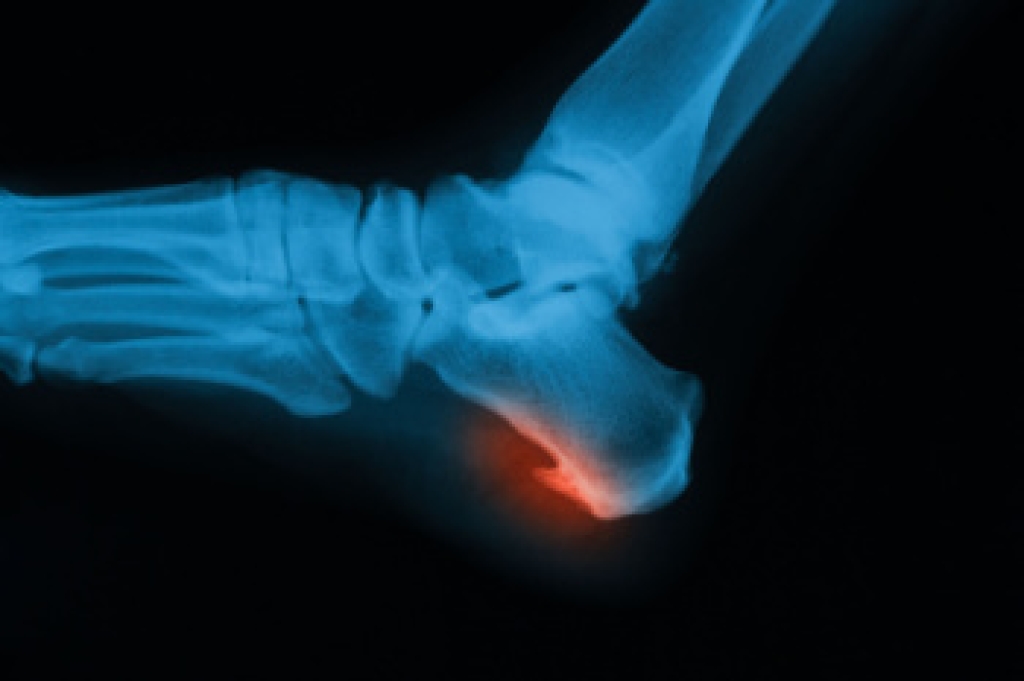

Heel spurs are another cause of pain. When the tissues of the plantar fascia undergo a great deal of stress, it can lead to ligament separation from the heel bone, causing heel spurs.